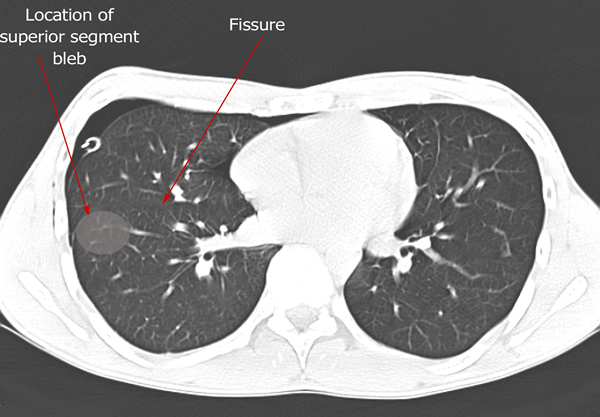

Patients who have had a second episode of spontaneous pneumothorax are those most likely to be considered for thoracoscopic pleurectomy and apical blebectomy. However, patients with a first episode of spontaneous pneumothorax who have a prolonged air leak (greater than 72 hours), incomplete expansion of the lung (Figure 1), bilateral pneumothoraces, associated hemothorax, tension pneumothorax (Figure 2), or a bleb on their CT scan (Figure 3) should be offered surgery at the time of the first occurrence [1]. Patients who have had a spontaneous pneumothorax and whose occupation places them at risk for a second episode or places them in a situation where medical intervention is not readily accessible should be considered for surgery. Therefore divers, pilots, submarine personnel, and those that work or live in the wilderness or space are suitable patients [1].

| Figure 1: Chest x-ray showing incomplete expansion of lung after chest tube placement. | Figure 2: Chest x-ray showing tension pneumothorax with mediastinal shift. | Figure 3: CT Scan showing apical bleb. |

| Figure 4: CT scan showing location of superior segment bleb. |

Patients who have had a previous operation for spontaneous pneumothorax where complete pleurectomy or bleb resection was not performed and who develop a recurrence should be offered re-operation. Prior surgery for pneumothorax is not a contraindication to use of a thoracoscopic approach, as pleural adhesions are relatively few in these patients. A CT scan of the chest readily identifies blebs most commonly seen at the apex of the lung but also in the superior segment of the lower lobe (Figure 4, Video 1 below).